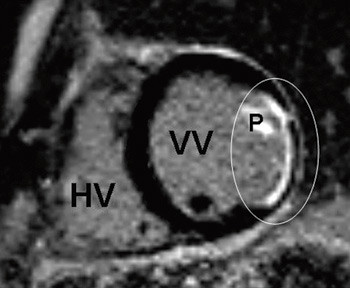

Kontrastbasert MR vil kunne avdekke uoppdaget gjennomgått myokardinfarkt, slik som vi fant hos en av pasientene som hadde angiografisk normale koronararterier. Ved myokardinfarkt på grunn av en okkludert koronararterie vil alltid kontrastoppladningen følge distribusjonsområdet til koronararterien og være subendokardial med varierende grad av transmuralitet (fig 2). Ved myokarditt vil kontrastoppladningen være epikardial og ikke følge koronararteriens forsyningsområde (fig 3). Det kan oppstå vansker med diagnostisering av myokardskade på grunn av myokarditt i forhold til myokardskade på grunn av myokardinfarkt dersom det samme området av myokard er rammet.